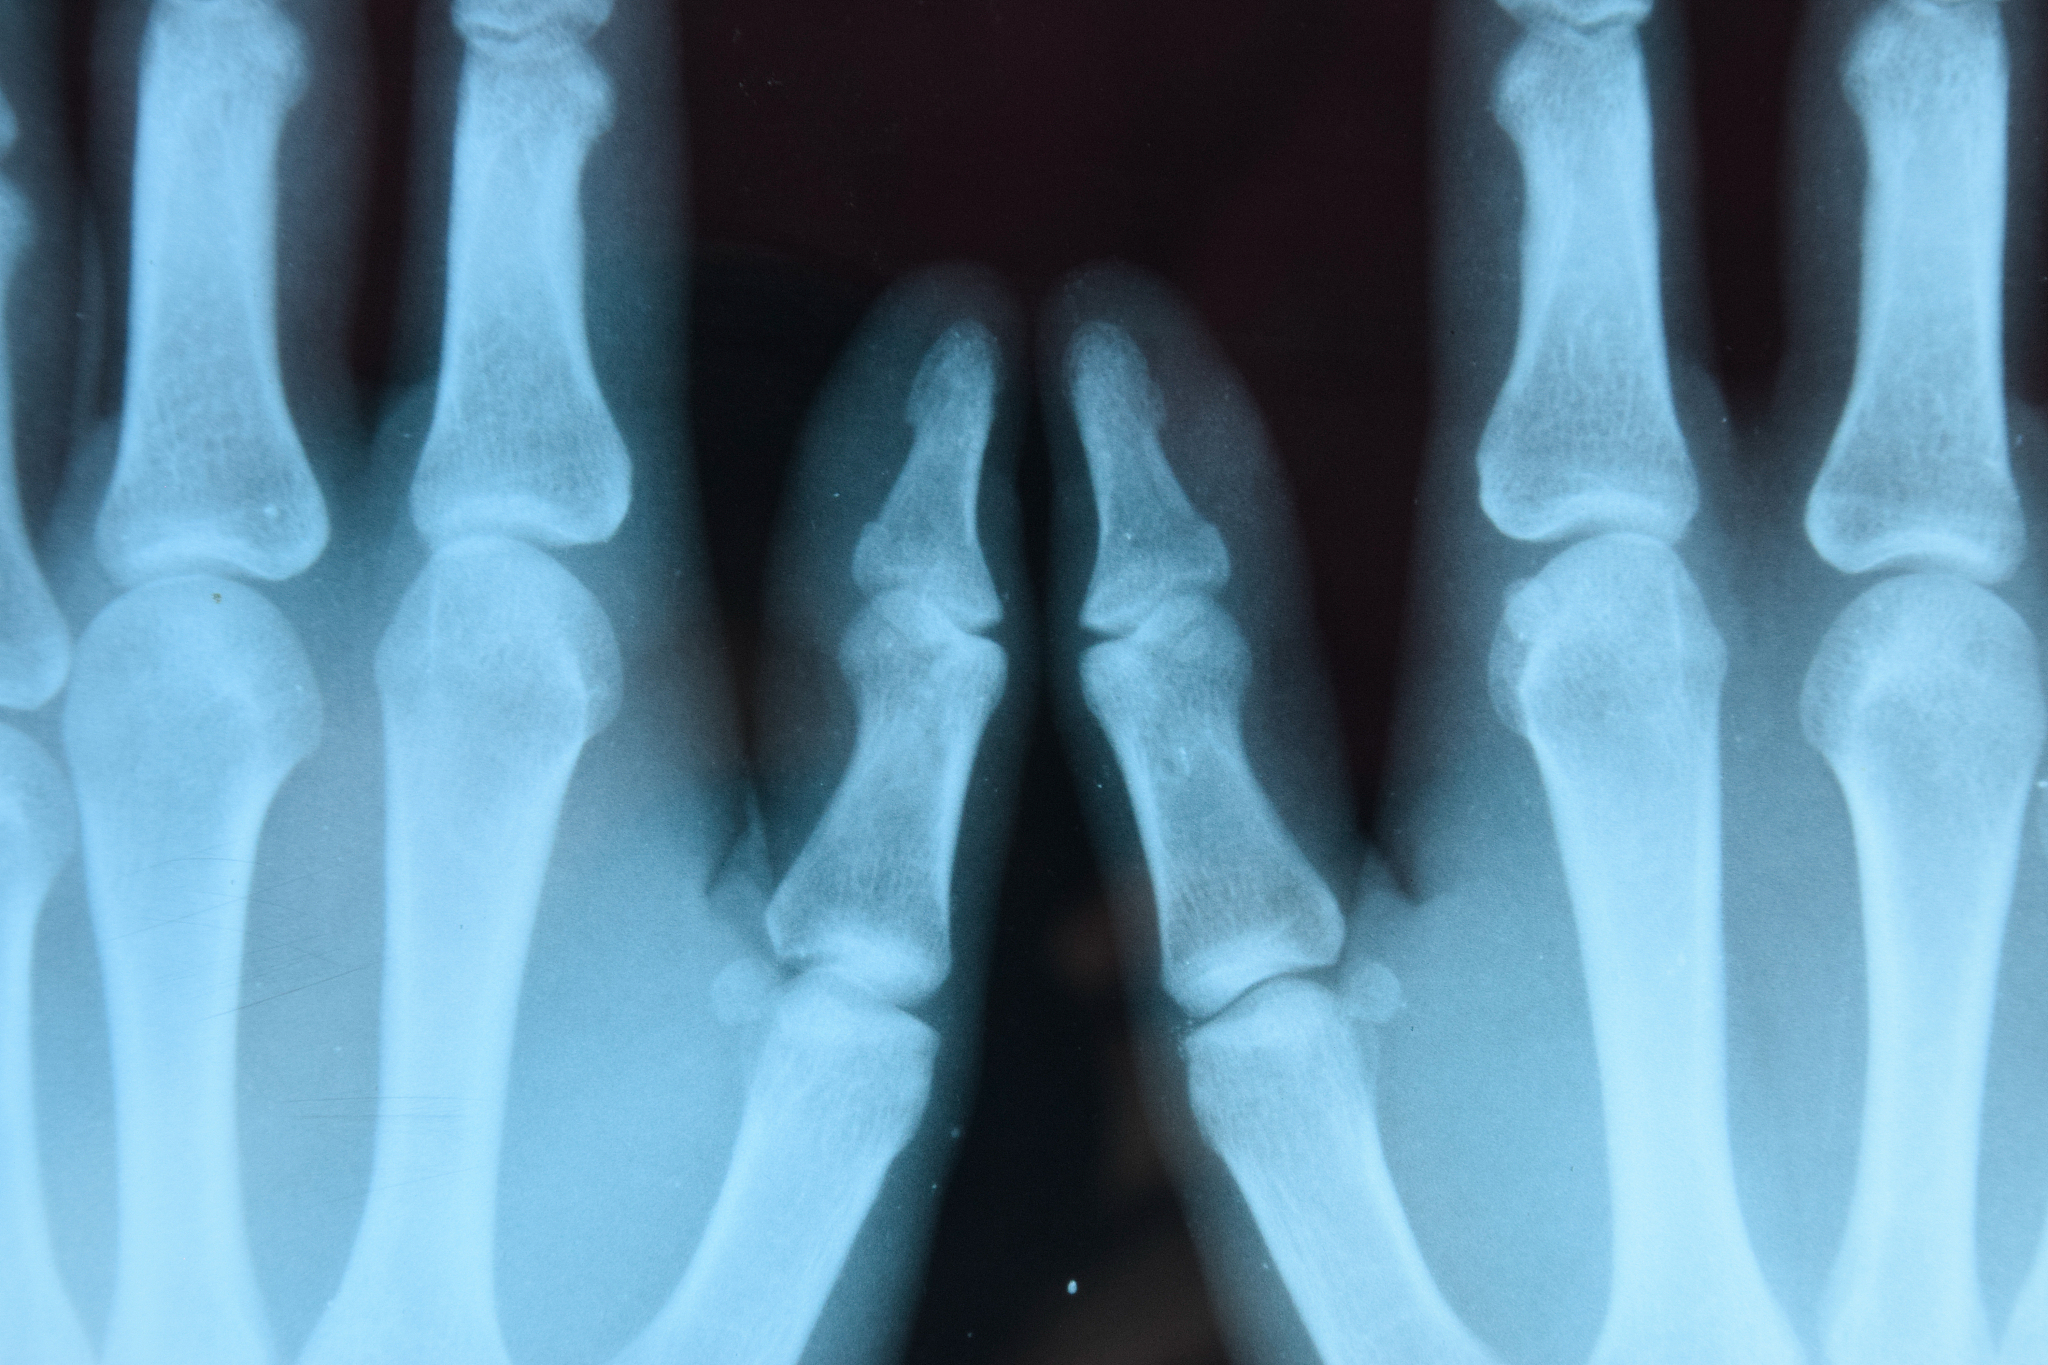

关节脱位类型中 复位及保持较 为困难的是臼骨后脱位因为臼骨后脱位时关节被卡住复位难度较大并且容易再次脱位。掌指关节呢?掌指关节也是容易脱位的关节之一特别是拇指掌指关节。由于手部经常进行各种动作和运动掌指关节容易受到外力伤害导致脱位。如果不及时进行复位和固定可能会导致手功能障碍和疼痛等问题。因此对于掌指关节的脱位要及时就诊并接受专业治疗。掌指关节复位及保持较为困难

的情况包括复杂性掌指关节脱位和伴有软组织损伤的掌指关节脱位。这些情况需要进行手术治疗,并在手术后进行康复训练。